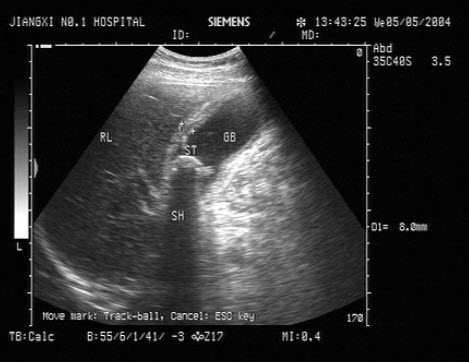

74、单项选择题

患者女47岁,皮肤、巩膜黄染,进行性加重2个月余,腹痛、腹胀,既往有胆结石病史。B超检查如图所示,根据超声声像图,诊断为()

A.胆总管癌并结石

B.胆总管胆泥淤积

C.胆总管结石

D.胆总管蛔虫

E.胆总管癌